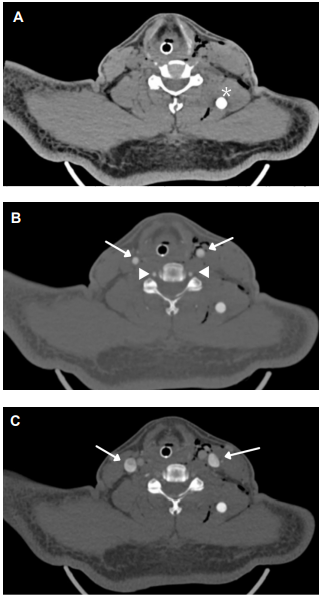

Por tratarse de un trauma cervical con aparente trayectoria transcervical, en un paciente estable hemodinámicamente, con un signo de sospecha de lesión vascular, e imposibilidad de valoración sintomática por la sedación e intubación orotraqueal, se decidió realizar una angiotomografía de cuello donde reportaron leve enfisema retrofaríngeo, laríngeo y en planos musculares (Figura 1). La tomografía descartó trayecto transcervical, lesión vascular, ósea, nerviosa o de órganos y se identificó un proyectil de caucho (proyectil de energía cinética) alojado en masa muscular paravertebral, con proximidad al musculo elevador de la escapula del lado izquierdo.

Debido a la sospecha de lesión de la vía aérea por la presencia de gas en el espacio visceral (Figura 2), se practicó una fibrobroncoscopia, que mostró adecuada movilidad de los pliegues vocales, sin lesiones supraglóticas, glóticas o traqueales.